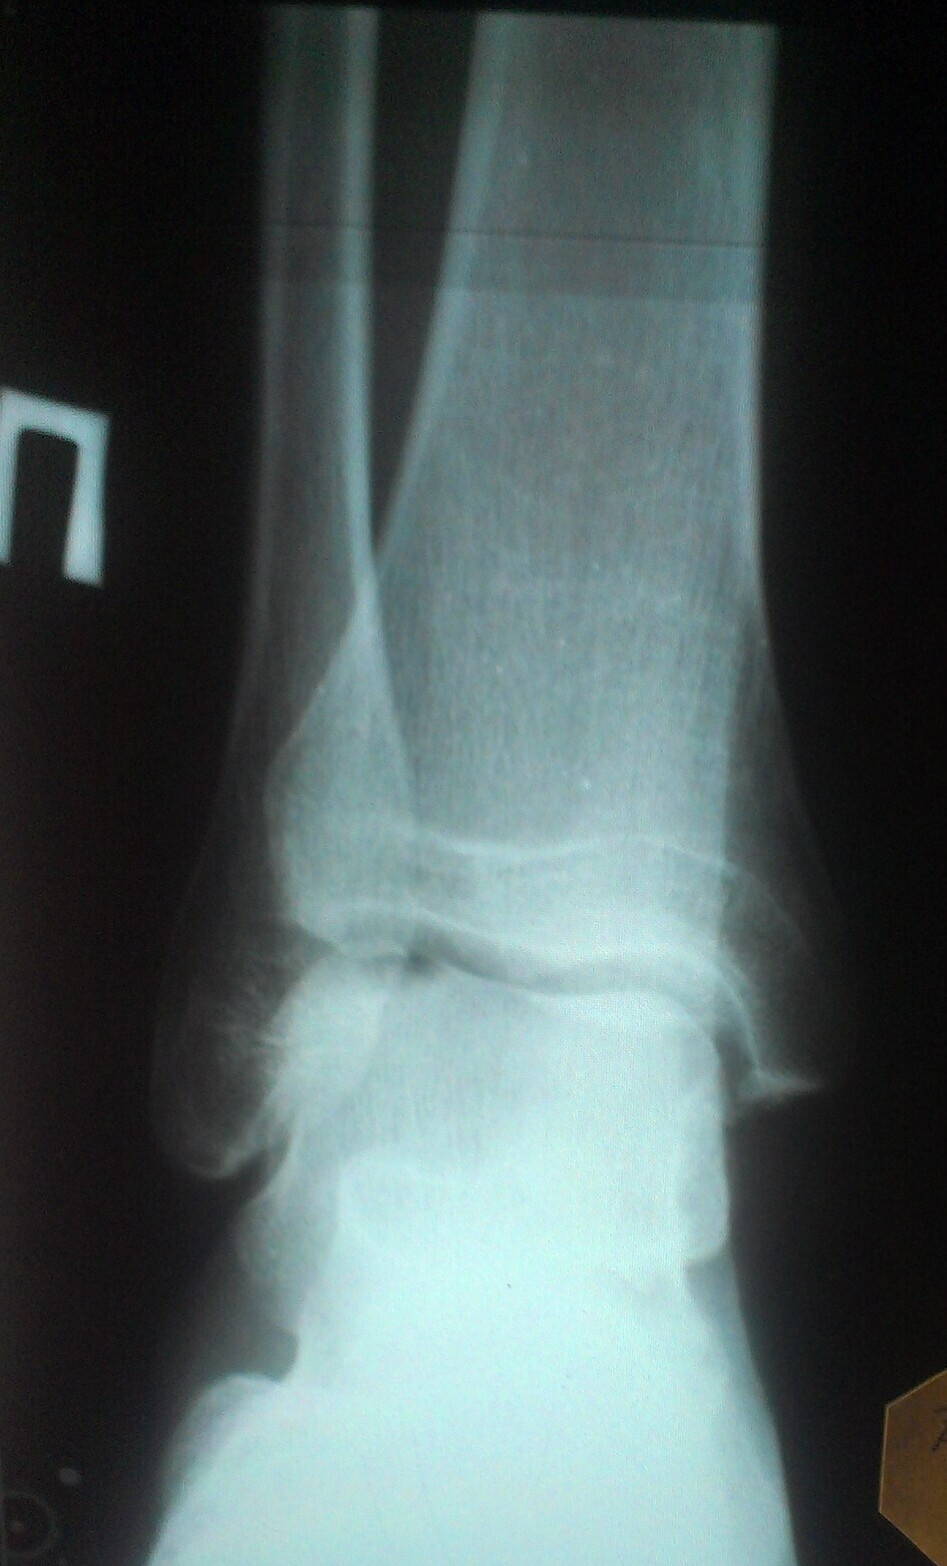

02.02.12 (4 травматалогия)

В 4й травматологии сделали рентген, сказали трещин пока не видно, но нужно будет еще позже проверить на повторном снимке. Перелома нет. Сказали повреждение связочного аппарата, повесили гипс на голень и стопу, гипс носил до 14ого, потом еще неделю дома носил повязки.

14.02.12 (студенческая)

В студенческой сделали повторный рентген, сказали трещин нет, на ногу внешне не смотрели. Сказали бинтовать эластичным бинтом и мазать долобене. Чуть чуть помазал, мотал бинтами долго.

7.06.12 (студенческая)

Снова в студенческую пошел так как не проходила нога. Сделали рентген, внешне ногу не смотрели. Сказали дисплазии нет, есть воспаление сустава, непонятно почему. Назначили компресы с Димексид+Гидрокартизон, мазь Дип-Хит и Фламидез таблетки 2шт/день в течении 10-12 дней.

5.02.13 (17 детская)

Осмотрели ногу, сделали рентген, было подозрение на кисту, которое не подтвердилось. Для уточнения пошел с рентгенами к професору, который сказал, что Болезнь Кенига.